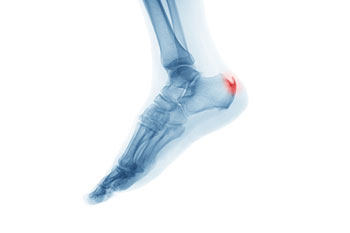

Heel spurs are typically diagnosed through a physical examination and imaging studies like X-rays. Treatment recommendations may include doing certain foot stretches, modifying your footwear, wearing orthotics, or using night splints. Over-the-counter medications can be used to relieve pain and inflammation. Surgical treatment may be considered if more conservative measures have failed to alleviate your symptoms, but surgery is rarely required for heel spurs.